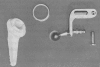

Background: Management of the cuff-deficient arthritic shoulder has long been challenging. Early unconstrained shoulder arthroplasty systems were associated with high complication and implant failure rates. The evolution toward the modern reverse shoulder arthroplasty includes many variables of constrained shoulder arthroplasty designs.

Questions/purposes: This review explores the development of reverse shoulder arthroplasty, specifically describing (1) the evolution of reverse shoulder arthroplasty designs, (2) the biomechanical variations in the evolution of this arthroplasty, and (3) the current issues relevant to reverse shoulder arthroplasty today.

Results: Results of the early designs were apparently poor, although they were not subjected to rigorous clinical research and usually reported only in secondary literature. We identified a trend of glenoid component failure in the early reverse designs. This trend was recognized and reported by authors as the reverse shoulder evolved. Authors reported greater pain relief and better function in reverse shoulder arthroplasty with the fundamental change of Grammont's design (moving the center of rotation medially and distally). However, current reports suggest lingering concerns and challenges with today's designs.

Conclusions: The history of reverse shoulder arthroplasty involves the designs of many forward-thinking surgeons. Many of these highly constrained systems failed, although more recent designs have demonstrated improved longevity and implant performance. Reverse shoulder arthroplasty requires ongoing study, with challenges and controversies remaining around present-day designs.